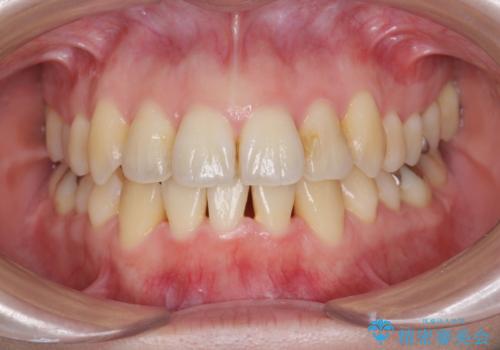

[ 総合歯科診療 ] がたつきの改善とセラミック治療

![[ 総合歯科診療 ] がたつきの改善とセラミック治療の症例 治療前](https://seimitsushinbi.jp/wp/wp-content/uploads/2024/03/f0f438a14c56b185411649f48b5b188c-500x350.jpg?v=1710833163)

![[ 総合歯科診療 ] がたつきの改善とセラミック治療の症例 治療後](https://seimitsushinbi.jp/wp/wp-content/uploads/2024/03/7212917eb9c4ef33050c52e7f9724490-500x350.jpg?v=1710833188)